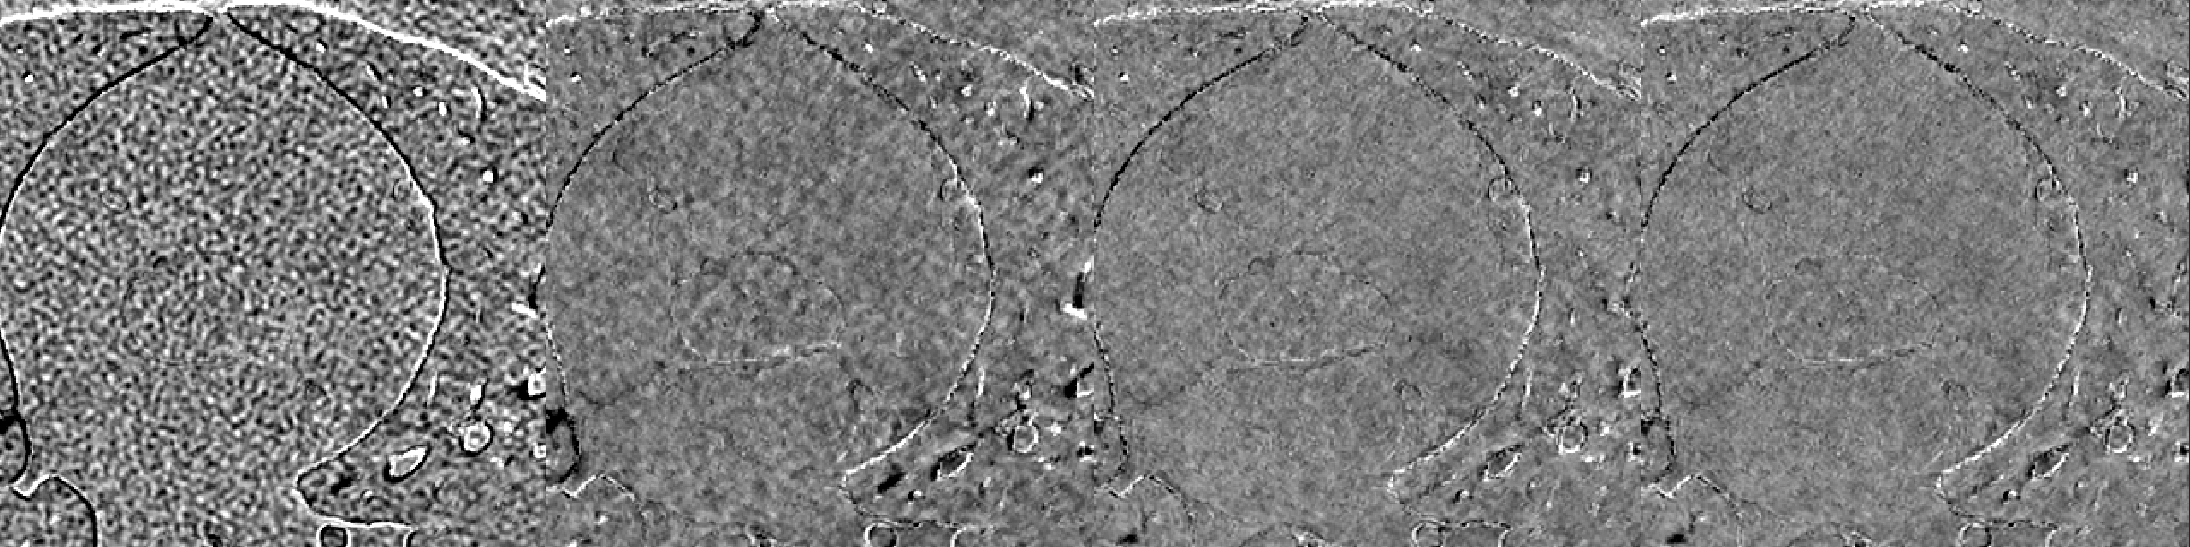

A cardiac FBP image was inferenced on the trained DL-MBIR network. Inference time for every network was between 4 and 6 seconds, and it goes up with the increase in the number of input channels. The MBIR version of the same exam was also available. Figure 3 shows a comparison, for 4 slices – LABEL:sub@fig:Image_10, LABEL:sub@fig:Image_50, LABEL:sub@fig:Image_90, and LABEL:sub@fig:Image_170 in the image volume, among MBIR image, FBP image, and the outputs of DL-MBIRZ𝐷𝐿-𝑀𝐵𝐼subscript𝑅𝑍DL\text{-}MBIR_{Z}, where Z=1, 3, 5𝑍135Z=1,\ 3,\ 5. Figure 4 shows a comparison, for the same slices in the image volume, among difference between images and the MBIR images. Figure 5 has a profile plot to show the comparison of DL-MBIRZ𝐷𝐿-𝑀𝐵𝐼subscript𝑅𝑍DL\text{-}MBIR_{Z} and FBP images w.r.t the MBIR images.

Refer to caption

(a)

(b)

(c)

(d)

Figure 4: Difference image w.r.t. MBIR. (left to right): FBP𝐹𝐵𝑃FBP, DL-MBIR1𝐷𝐿-𝑀𝐵𝐼subscript𝑅1DL\text{-}MBIR_{1}, DL-MBIR3𝐷𝐿-𝑀𝐵𝐼subscript𝑅3DL\text{-}MBIR_{3}, DL-MBIR5𝐷𝐿-𝑀𝐵𝐼subscript𝑅5DL\text{-}MBIR_{5}. LABEL:sub@fig:Error_10, LABEL:sub@fig:Error_50, LABEL:sub@fig:Error_90 and LABEL:sub@fig:Error_170 represent different slices in the image volume. WW/WL 150/0 HU.

Visually, all DL-MBIR images bear close resemblance to the MBIR images in figure 3. It is confirmed by the difference images in figure 4. In the profile plot of Figure 5, the DL-MBIR profiles closely follow that of MBIR.